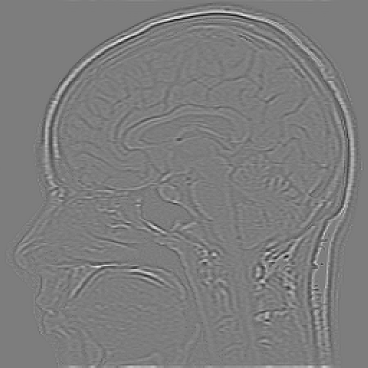

Typically the structural component contains the main components of the image, which is represented by the lower frequencies. The textural component contains the finer details like edges or high oscillations. These components are included in the high frequencies of an image. Therefore we introduce the Riesz potential, which captures the high frequencies, as the inverse of the fractional Laplacian. In Figure 1 we illustrate a decomposition into these components. This paper contains two main results. First we derive a rigourous error estimate for the bilevel problem in the case of spectral approximation. The numerical realization is easy to implement and in comparison to the ROF model much faster. Second we introduce a new image decomposition model, which has promising results in simultaneous image denoising and decomposition. To the best of our knowledge, this is the first work using fractional models in image decomposition. Moreover, we point out, that fractional differential operators are applicable in case of image denoising and decompositon. The use of fractional diffential operators in other image processing areas is a point of future research.